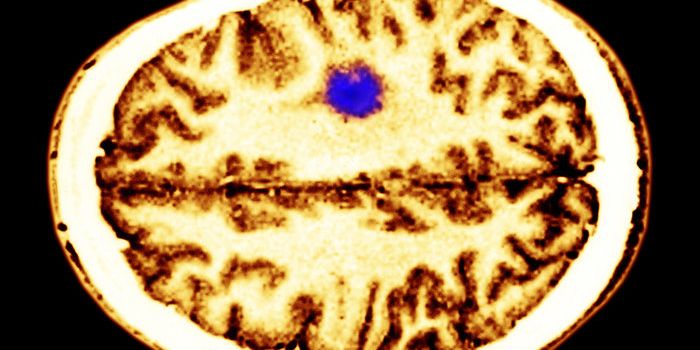

APR 24, 2015CancerThe simple act of thinking can accelerate the growth of many brain tumors.That's the conclusion of a paper in Cell publi ...

JAN 07, 2022CancerThe blood-brain barrier (BBB) describes the complex vasculature network that delivers oxygen and nutrients to the brain. ...